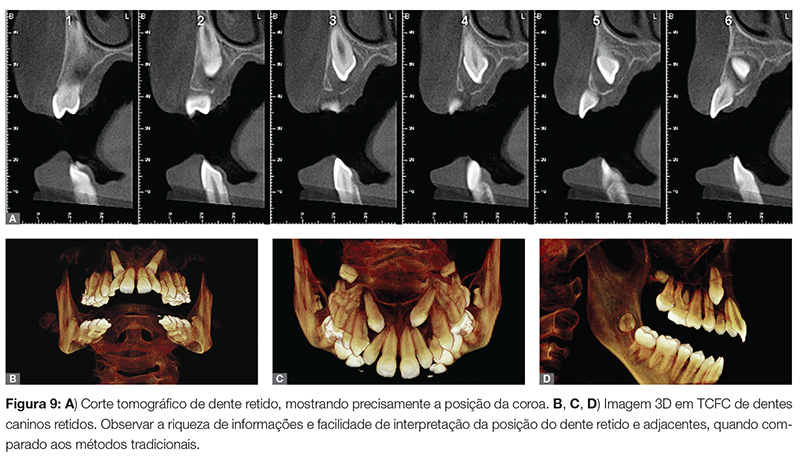

Mossaz et al.8 realizaram TCFC em 82 pacientes com dentes supranumerários para avaliar a localização e as características morfológicas desses dentes e para verificar a extensão de reabsorção radicular dos dentes adjacentes. Após a análise das imagens por dois ortodontistas, independentemente, dados sobre os dentes retidos e adjacentes foram compilados e estudados. Eles concluíram que o uso de TCFC proporciona uma informação 3D precisa sobre a localização e a forma do dente supranumerário retido, assim como a prevalência e o grau de reabsorção radicular dos dentes vizinhos, com moderada a alta correlação entre os examinadores (Fig. 7, 8, 9).

» Dentes retidos.